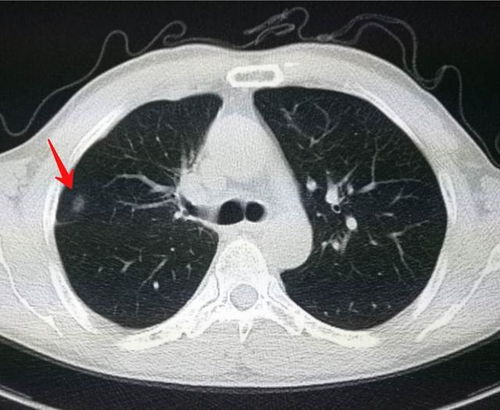

惊!术后一年肺结节竟癌变,医生凭经验手摸切错部位 本文讲述了李女士术后一年发现肺结节不仅未消失反而癌变的故事,揭示了手术过程中定位针“失踪”导致医生凭经验手摸切错部位的问题,引发社会广泛关注。 腾讯热点 2024年12月27日 23:40 0 点赞 0 评论 87 浏览